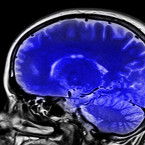

Parkinsonova choroba je jedním z nejčastějších degenerativních onemocnění nervové soustavy. Objevuje se hlavně u lidí starších...

Tato degenerativní choroba ovlivňuje nervový systém a všechny části těla, které pomocí tohoto systému ovládáme. Tuto nemoc zatím...

Jak se Parkinson projevuje, léčí a kolik stojí jeho léčba ve Středočeském kraji? Víte, že při něm odumírají buňky produkující...

Typický je jakýsi pomalý a bezděčný třes, který je nápadný především v klidu, ale tato nemoc může začínat i jako poměrně...